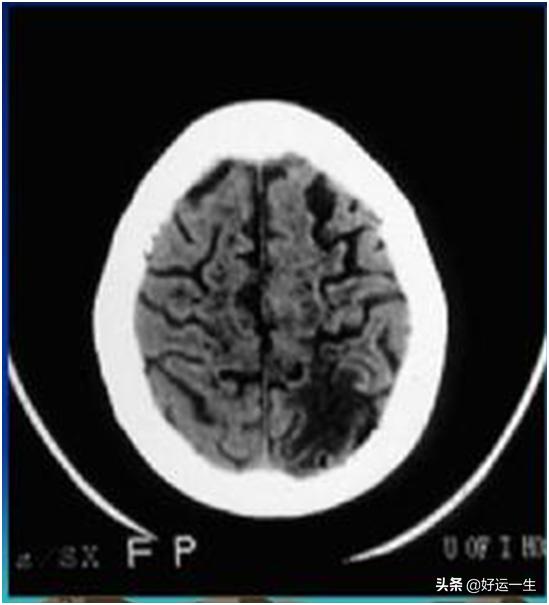

脳梗塞は、医学的には「低濃度陰影」と呼ばれる黒い斑点として見られる。これらの場所が病変部位である。図2